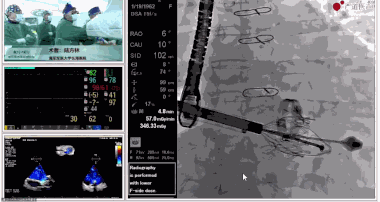

▲瓣膜植入前右心室造影

▲瓣膜植入過(guò)程